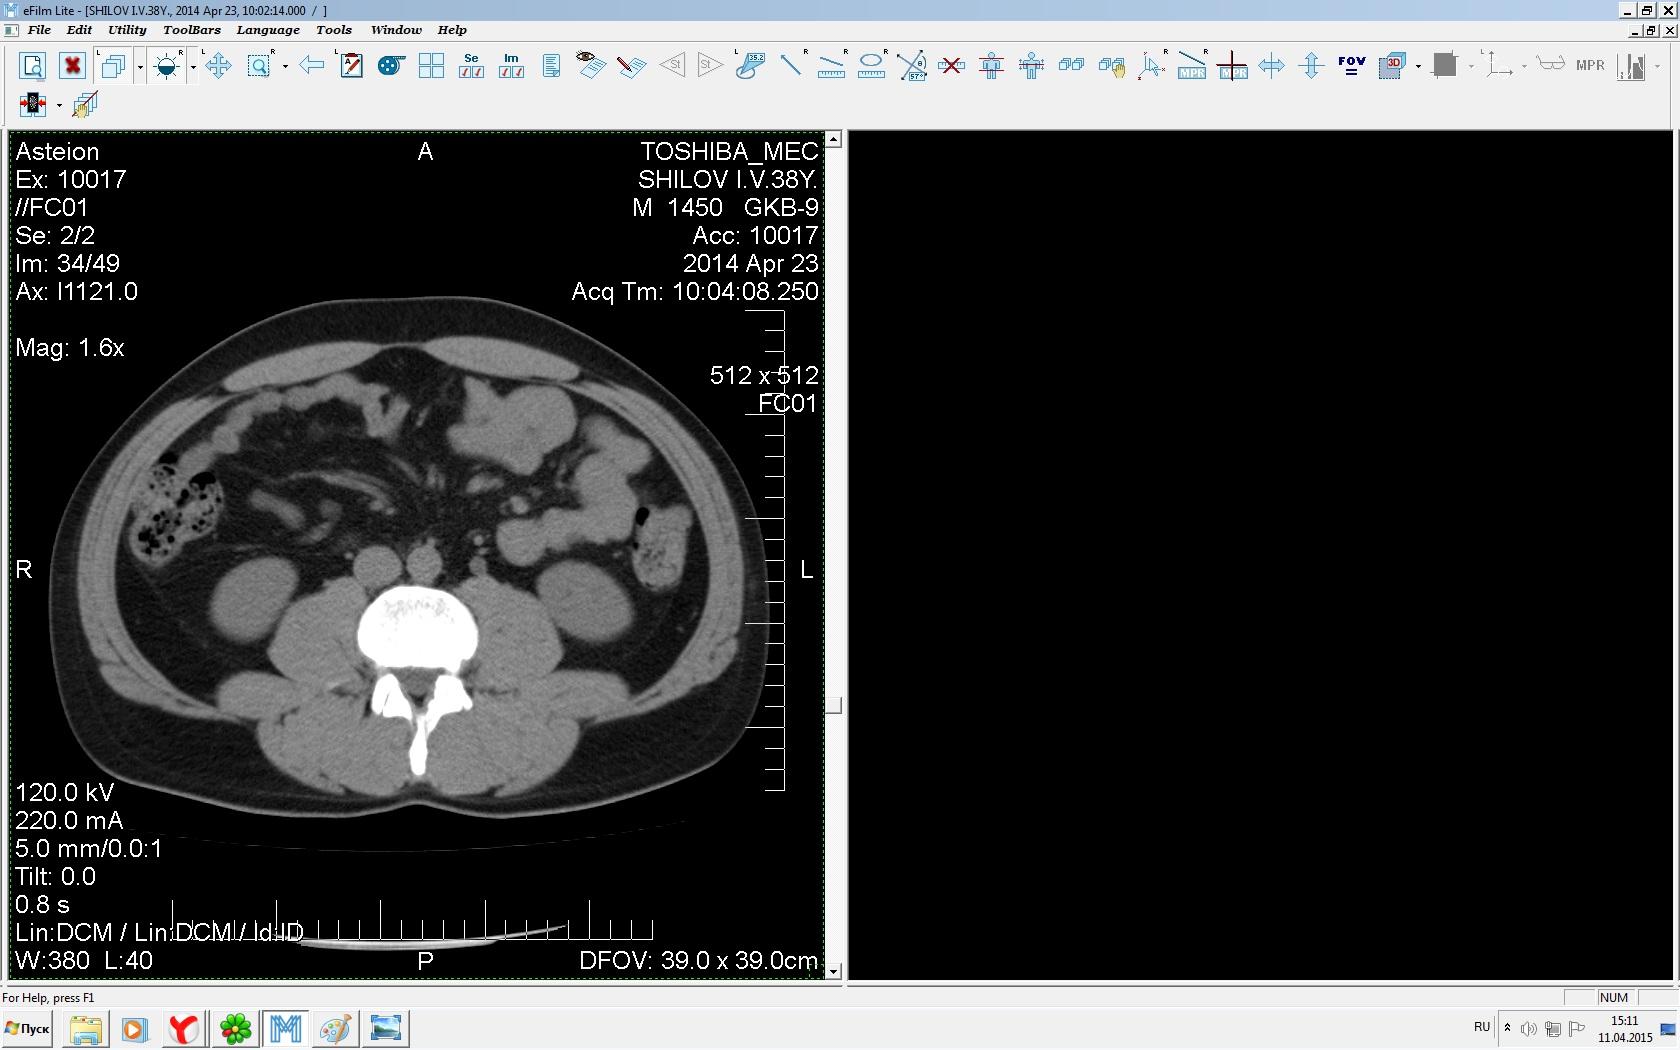

Здравствуйте. У меня киста левой почки. Из заключения: левая почка увеличена, деформирована за счёт наличия в среднем сегменте округлого жидкостного +6, +15 HU образования 66х53 мм, деформирует, поддавливает чаше-лоханочную систему. Сосудистые ножки структурные. В урологии мне сперва предложили лапароскопию, когда я лёг на операцию - изменили на полостную в связи со сложностью. Потом сказали что шансов вырезать кисту без почки практически нет. Даже если кисту удалить чудесным способом, то почка всё равно сложится и не будет работать. В итоге операцию отменили. Скажите, пожалуйста, есть ли современный метод удалить кисту и сохранить почку в моём случае? Томография почки в приложениях. Заранее благодарю.

Эту кисту можно просто пропунктировать, аспирировать и склерозировать - под местной анестезией. Ничего сверхестетственного не определяется по данным КТ. Можете написать мне на почту. aristova-tatyana@mail.ru